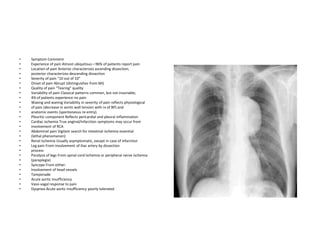

AngioTAC

AngioTAC 3d